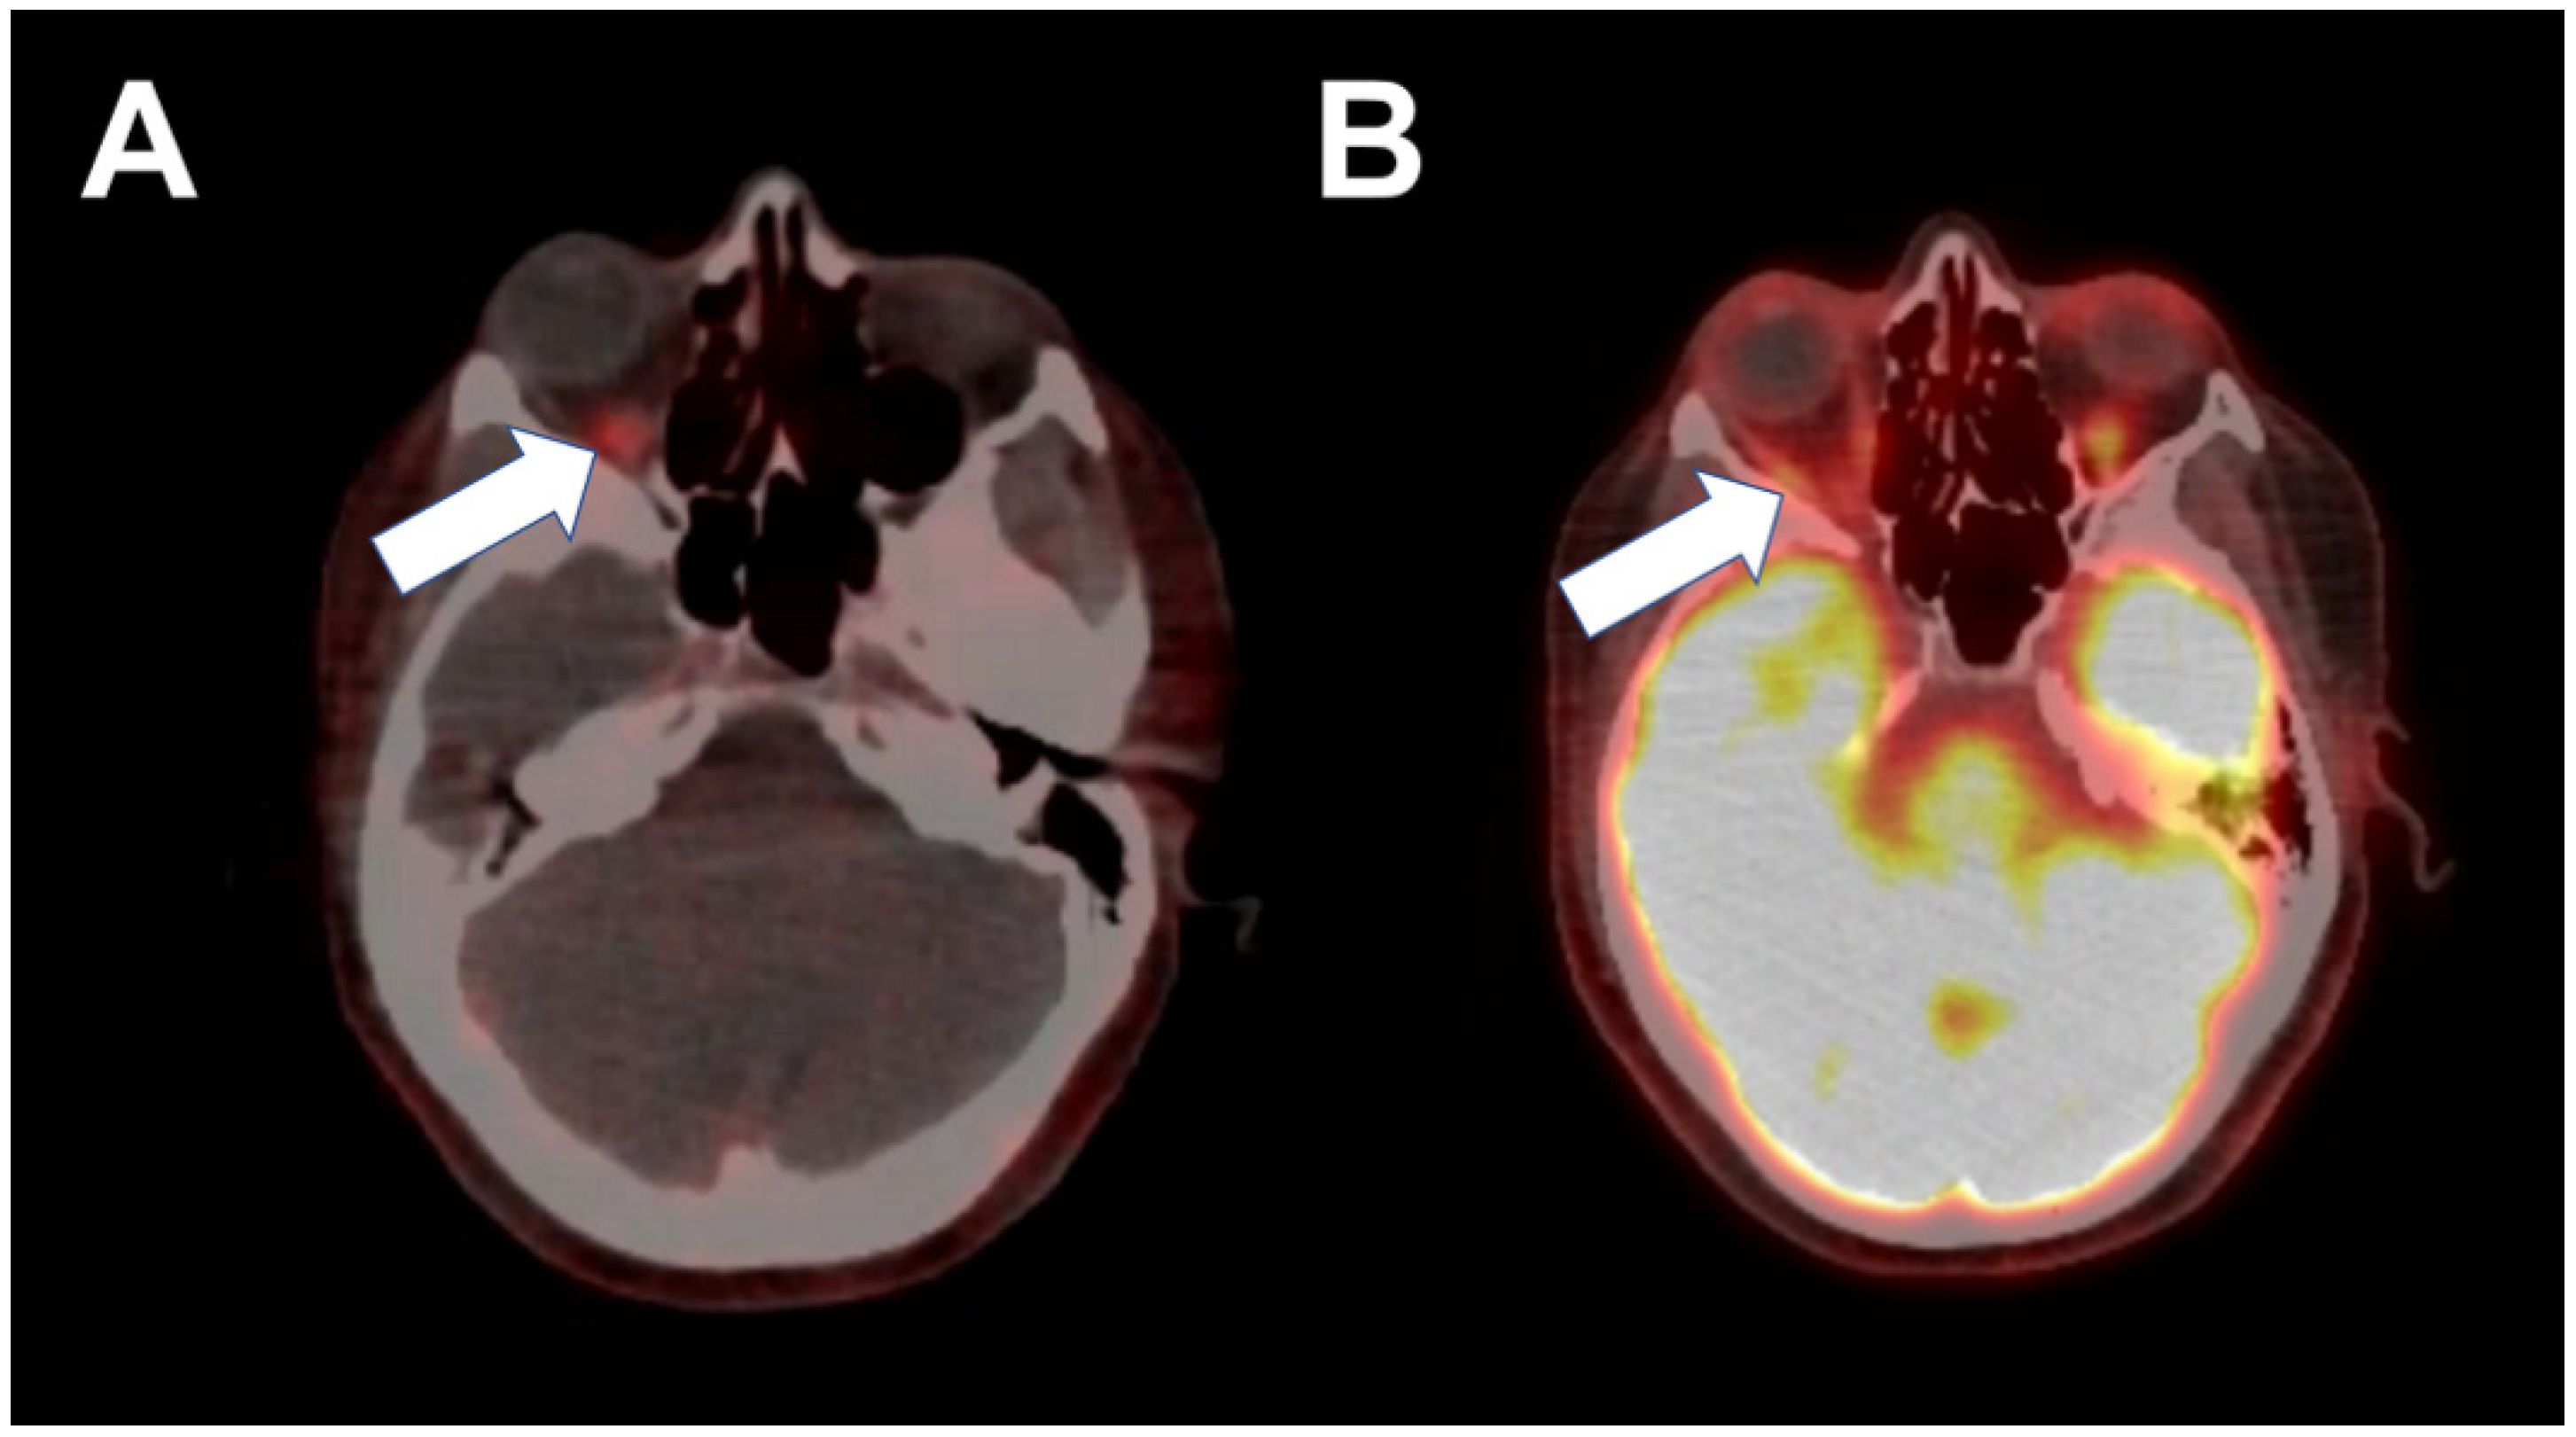

2. Case 1